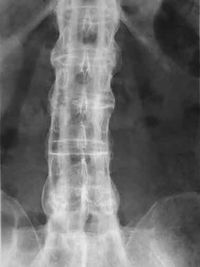

- Xray lumbar/sacroiliac: The earliest changes in the sacroiliac joints shows erosions and sclerosis

- Progression of erosions leads to pseudo widening of the joint space and bony ankylosis AKA "Bamboo Spine"